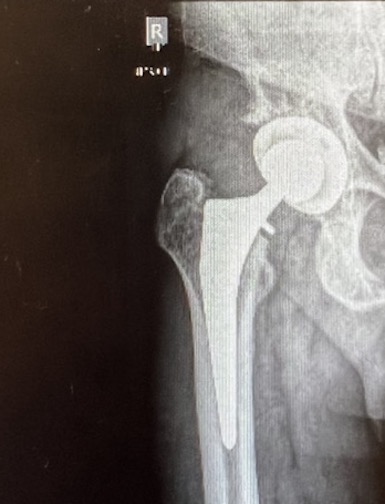

I had an appointment in the neighborhood with the orthopedic doctor who fixed my gimpy hip.

He gave me the green light of a successful outcome after viewing new X-rays.

I don’t know about everyone else, but this image is part creep-out, and part mobility blessing.

I thanked him for the nice scar. Dr. Huff called it a bikini scar. My description was a Speedo scar.